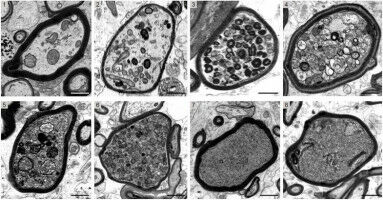

Multiple sclerosis (MS) affects millions of people worldwide, and there is currently no cure for this disease of the central nervous system. Damage to the nerve fibres, also called axons, is responsible for the severity of MS in patients and for the course of the disease. And myelin, which is the protective layer around axons, plays a key role in this process.